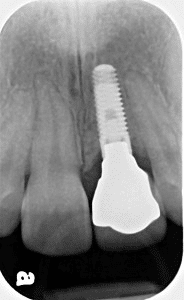

This twenty three year old woman presented to us as a teenager with her maxillary central incisor failing. The tooth was replaced with a bone graft and a removable appliance, which provided a temporary replacement tooth during her teenage years. After waiting an appropriate amount of time until she had stopped growing, we inserted the implant, itself, using a special CT Scan generated surgical guide so that it was placed at the right depth and angulation. Her dentition has been rejuvenated.

The timing of implant placement is crucial, especially in young patients. We waited until skeletal growth was complete to ensure the implant would integrate properly and maintain its position for decades. The use of guided surgery with the CT Scan ensured that the implant was positioned exactly right, allowing for a natural-looking crown that perfectly complements her smile.

CT scan surgical guide for precision implant placement

The new implant-supported maxillary central incisor was created using a special CT Scan generated surgical guide to ensure precise placement at the right depth and angulation. Her dentition has been rejuvenated with a restoration that looks and feels completely natural. She can now smile, speak, and eat with full confidence.